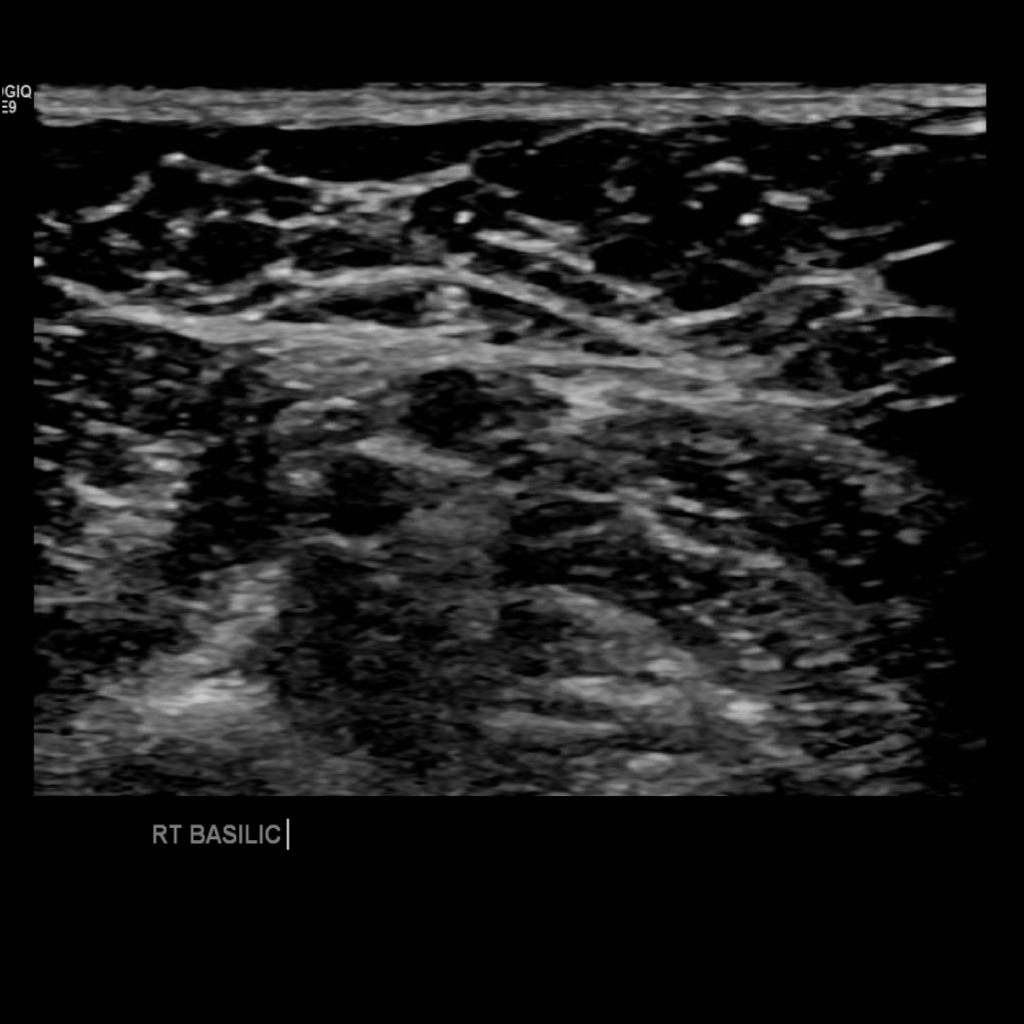

Upper extremity clots are commonly caused by venous lines, especially PICC lines (peripherally inserted central catheter). The basilic vein is the typical location for insertion of PICC lines, thrombosis can be seen in up to 70-80% according to some studies, especially the longer the line is in place.

Scan the basilic vein in grey scale, compression, color doppler and spectral doppler

Thrombus of the right basilic vein